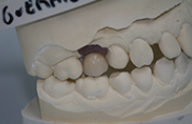

Cas cliniques

Chaque cas est unique nous essayons toujours de privilégier la meilleure solution pour le patient, d'abord d'un point de vue thérapeutique mais aussi d'un point de vue financier.

Ces cas cliniques sont une illustration pédagogique de traitements odontologiques. Leur objectif est de mettre en image des soins dentaires pour une meilleure compréhension de ceux-ci.